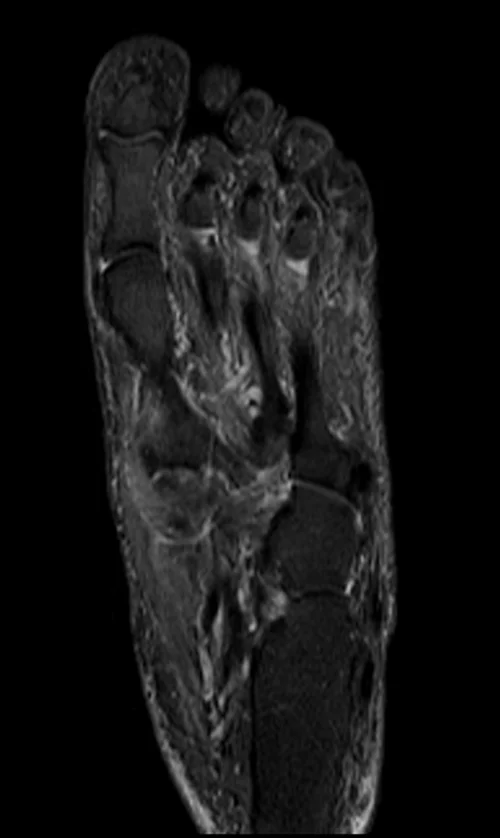

MRI FOOT CORONAL STIR IMAGE 1 - MRI